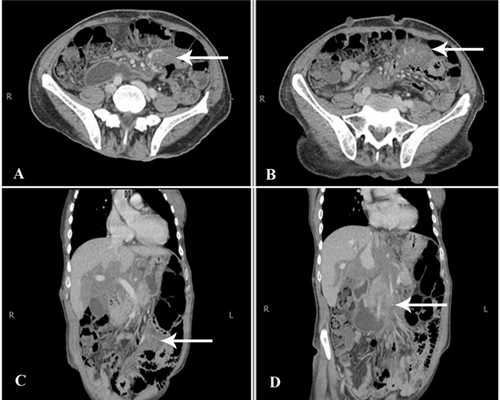

Для определения локализации опухолей при нейрофиброматозе Реклингхаузена проводится КТ и МРТ позвоночника, МРТ и КТ головного мозга. Диагностика аномалий скелета осуществляется путем проведения рентгенографии позвоночника и черепа. При диагностике НФ2 обязательным является исследование слуха: аудиометрия, тест Вебера, импедансометрия, электрокохлеография, исследование вызванных слуховых потенциалов.

- КТ или МРТ головного мозга, позвоночного столба, внутренних органов поможет оценить их структуру и функциональность. Эти исследования применяются для выявления опухолевых разрастаний в подкожной клетчатке или на внутренних органах.